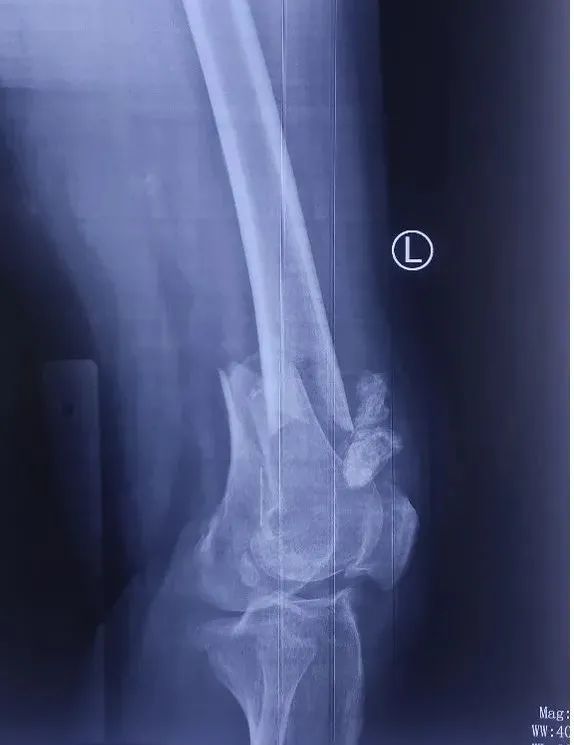

患者是一位高龄女性,因一次滑倒意外致左膝关节受伤,由此导致左股骨远端骨质疏松性骨折,伤后来到积水潭医院创伤骨科住院治疗。

吴新宝团队对患者检查后发现患者系典型老年骨质疏松性骨折,膝关节周围有明显老年退行性改变;股骨远端大量骨性增生导致骨折部位解剖形态与青壮年成人有明显差异,股骨前弓明显增大;同时老年患者骨愈合能力下降,容易发生骨折不愈合,内固定物失效等并发症。如何更好地解决老年骨质疏松性骨折这一临床问题,降低手术并发症是骨科医生面临的一个临床挑战。

吴新宝团队术前详细规划,反复推演手术流程。2021年9月27日,在短短不到1小时的时间内,手术团队按照手术设计顺利完成了骨折的复位固定。术中影像显示,骨折解剖复位,定制钢板位置得当,螺钉位置理想,完美实现了术前规划的手术目标。